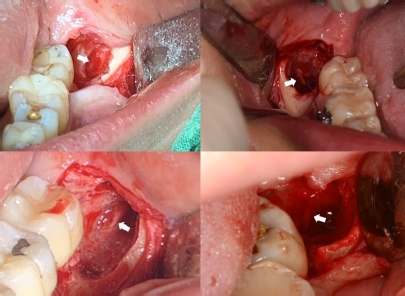

이들은 모두 치아가 정상적인 각도로 자라나지 않거나 숨거나 기울어져 있는 매복 사 랑니여서 수술적 발치가 요구됐다. 이 중 69건은 발치 후 드러난 치아 안쪽 공 간에서 하치조 신경이 관찰됐으며, 219건은 하치조 신경이 관찰되지 않았다.

발치 후 하치조 신경이 관찰된 것은 하치조 신경이 사랑니와 완전히 붙어 있었던 것으로, 발치 시 치아의 작은 움직임으로도 신경이 손상될 가능성이 있다.

분석 결과 수술 중 하치조 신경이 관찰된 69건 중 4.3%(3건)에서 신경손상이 발생했 고, 노출되지 않은 219건의 경우에서는 신경 손상이 발생하지 않았다.